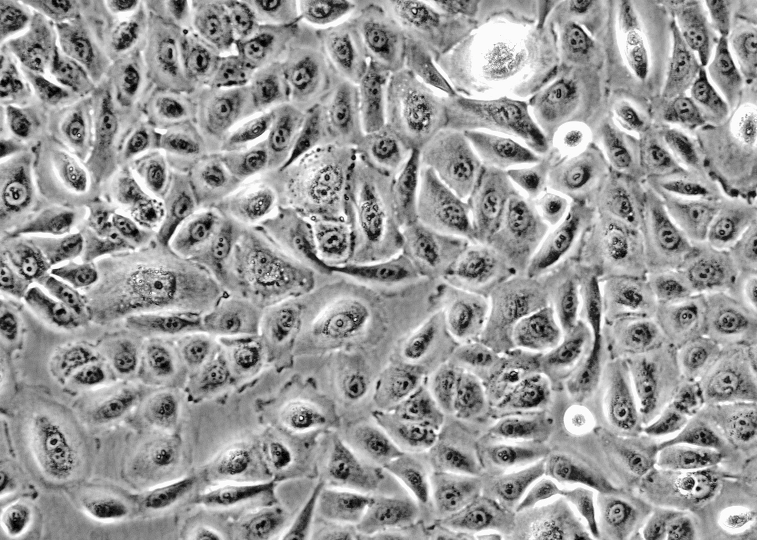

生长特性:贴壁细胞

细胞形态:上皮细胞样

背景描述:MDA-MB-231人乳腺癌细胞(通过STR鉴定)是从一名51岁的白人女性乳腺癌患者的胸水中分离建立的。MDA-MB-231细胞表达EGF受体、TGF-α受体和WNT7B癌基因。MDA-MB-231细胞在裸鼠和ALS处理的BALB/c小鼠中,能形成低分化腺癌(Ⅲ级)。